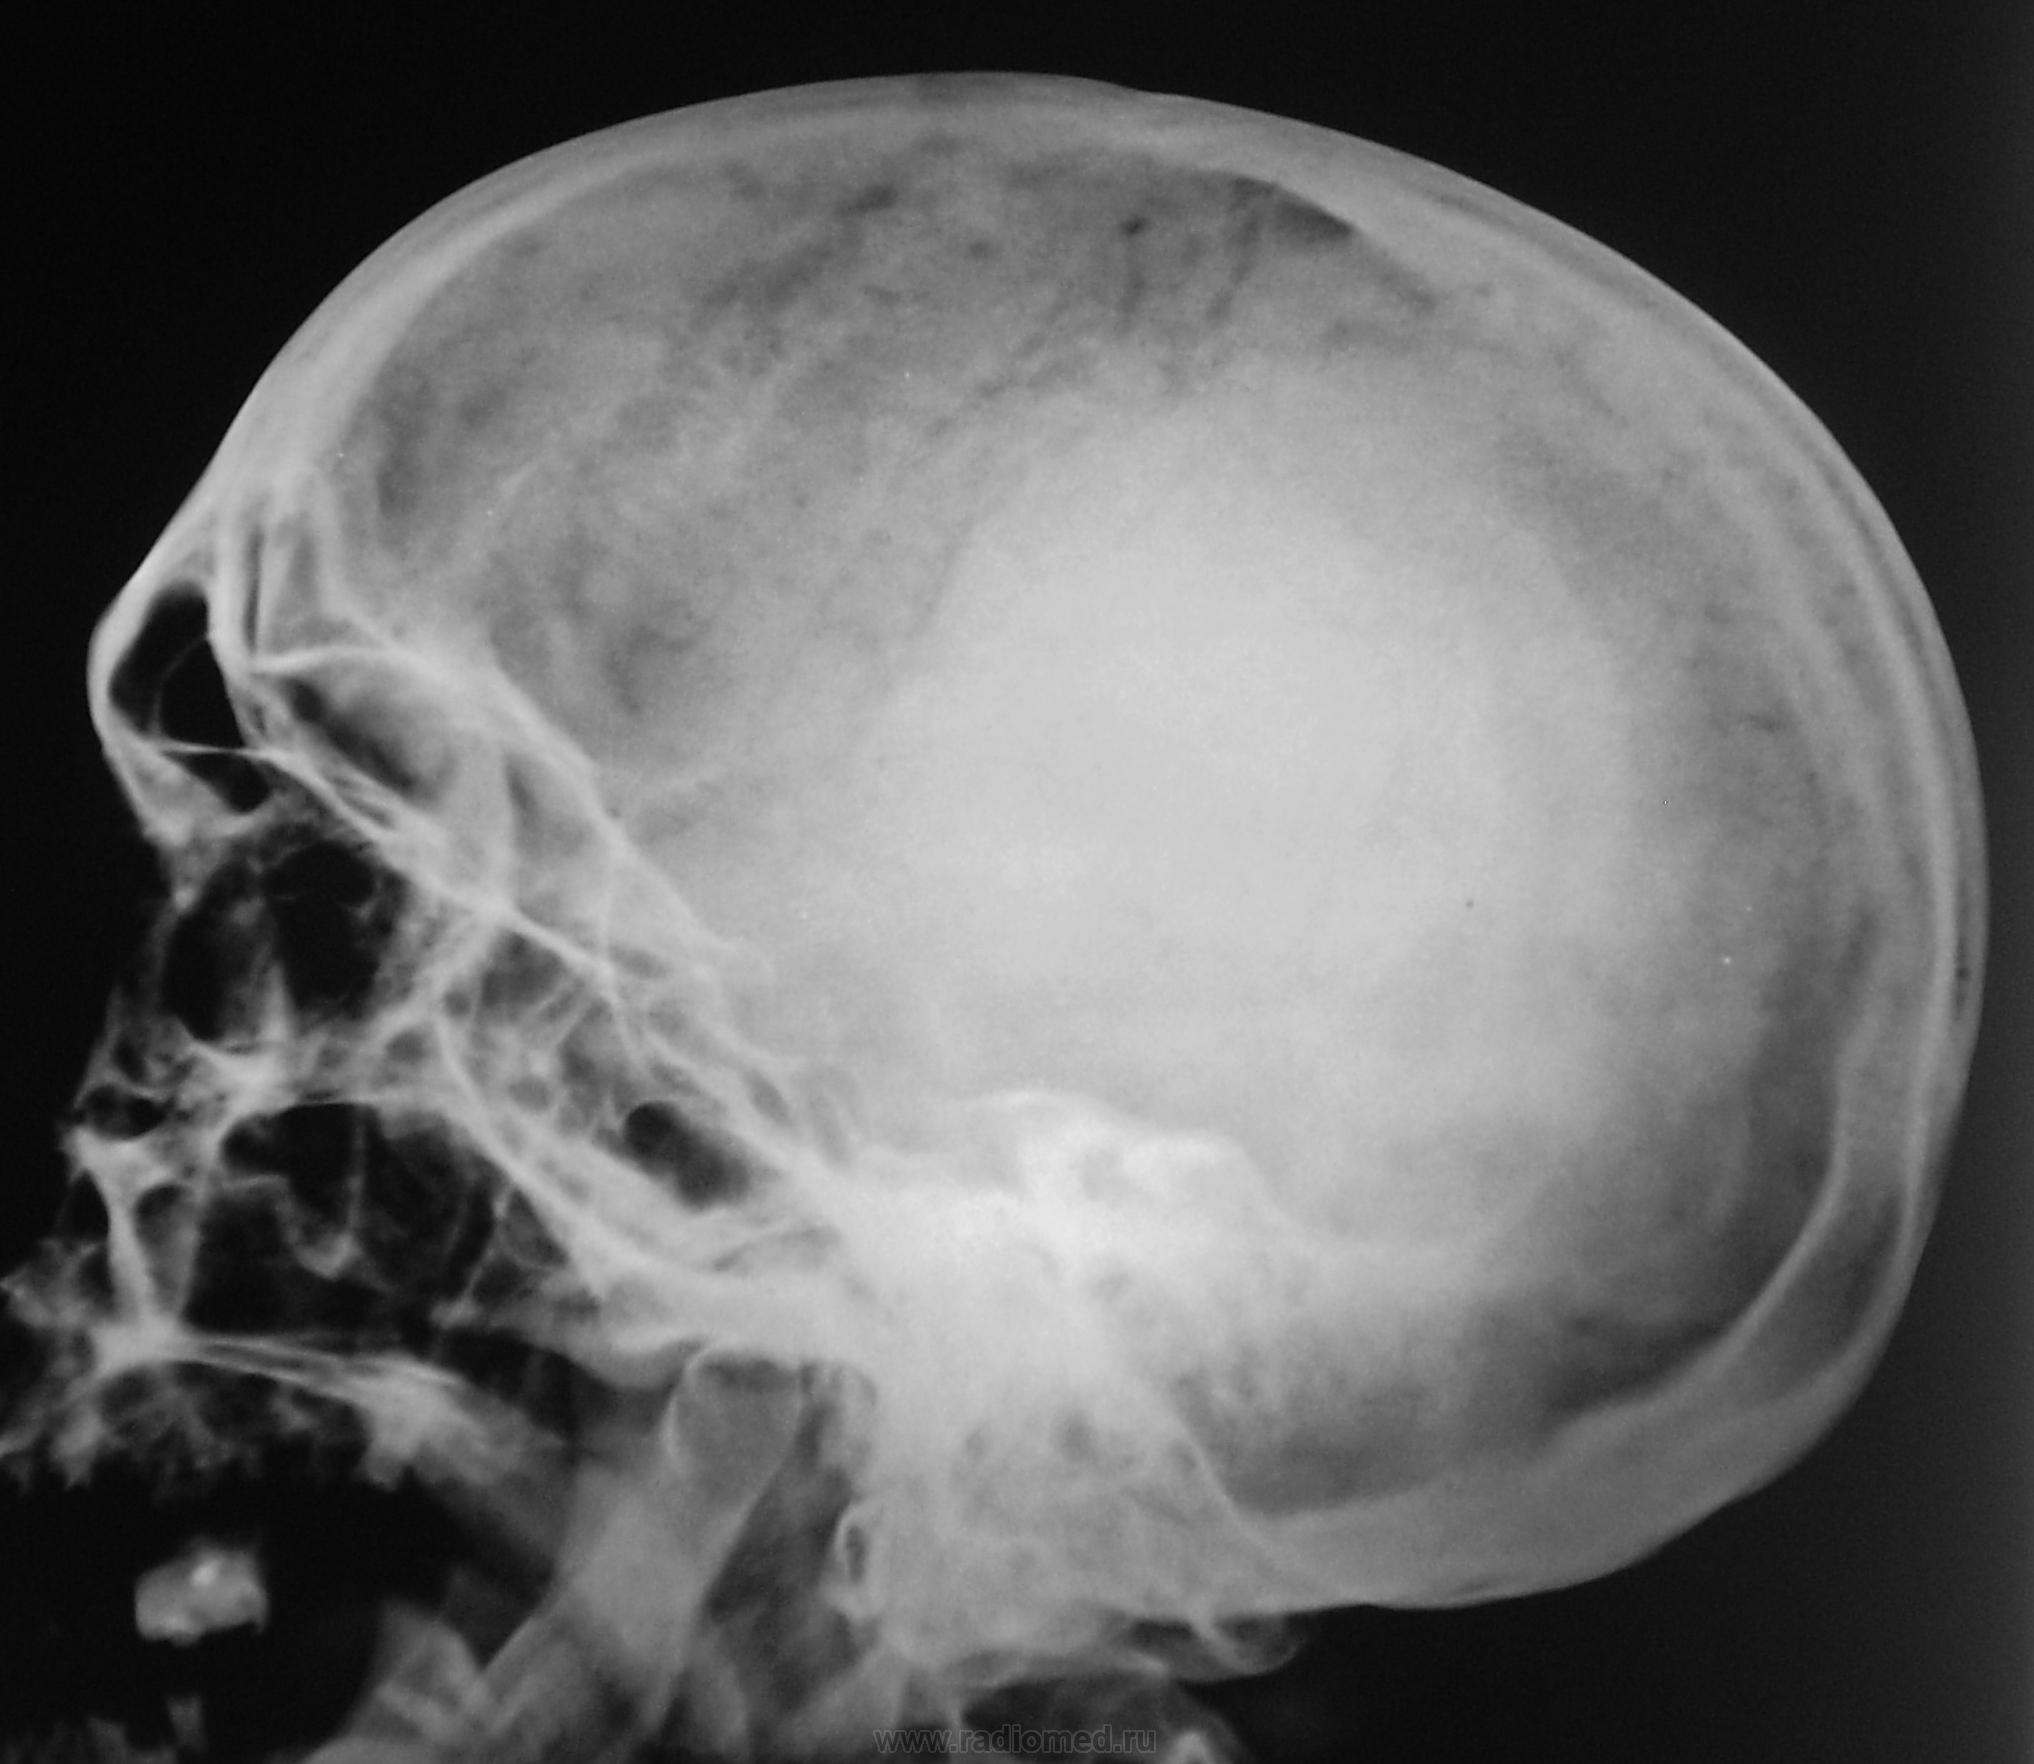

Рентгенография черепа и позвоночника: изображение и диагностика